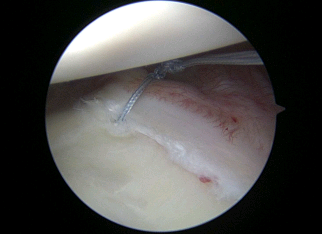

The patient is an elite level pitcher with decreased internal rotation, posterior labral fraying, and infraspinatus rotator cuff symptoms. His posterior labrum has become calcified on xrays and he has non-displaced posterior labral tearing on MRA. He has failed physical therapy and continued posterior impingement symptoms with throwing/pitching. At the time of shoulder arthroscopy, his posterior labrum was frayed (photo 1) and this was debrided. The undersurface of his infraspinatus is inflamed but not torn (photo 2). The posterior capsule is inflamed, stiff, and thickened (photo 3). The posterior capsule is released with the use of an arthroscopic scissors (photo 4). After release, the patients range of motion returned to that of the other side. He returned to pitching and went on to enter the MLB Draft.